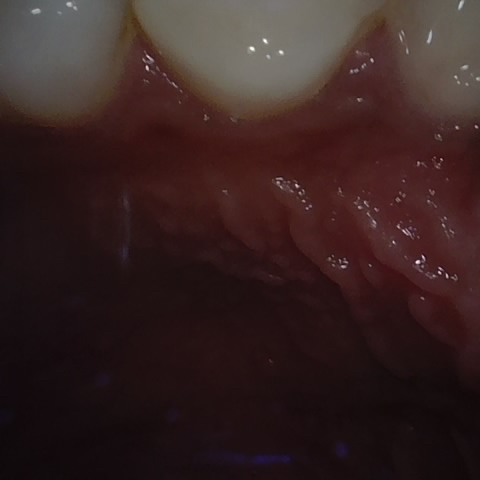

Annotated as "Good"